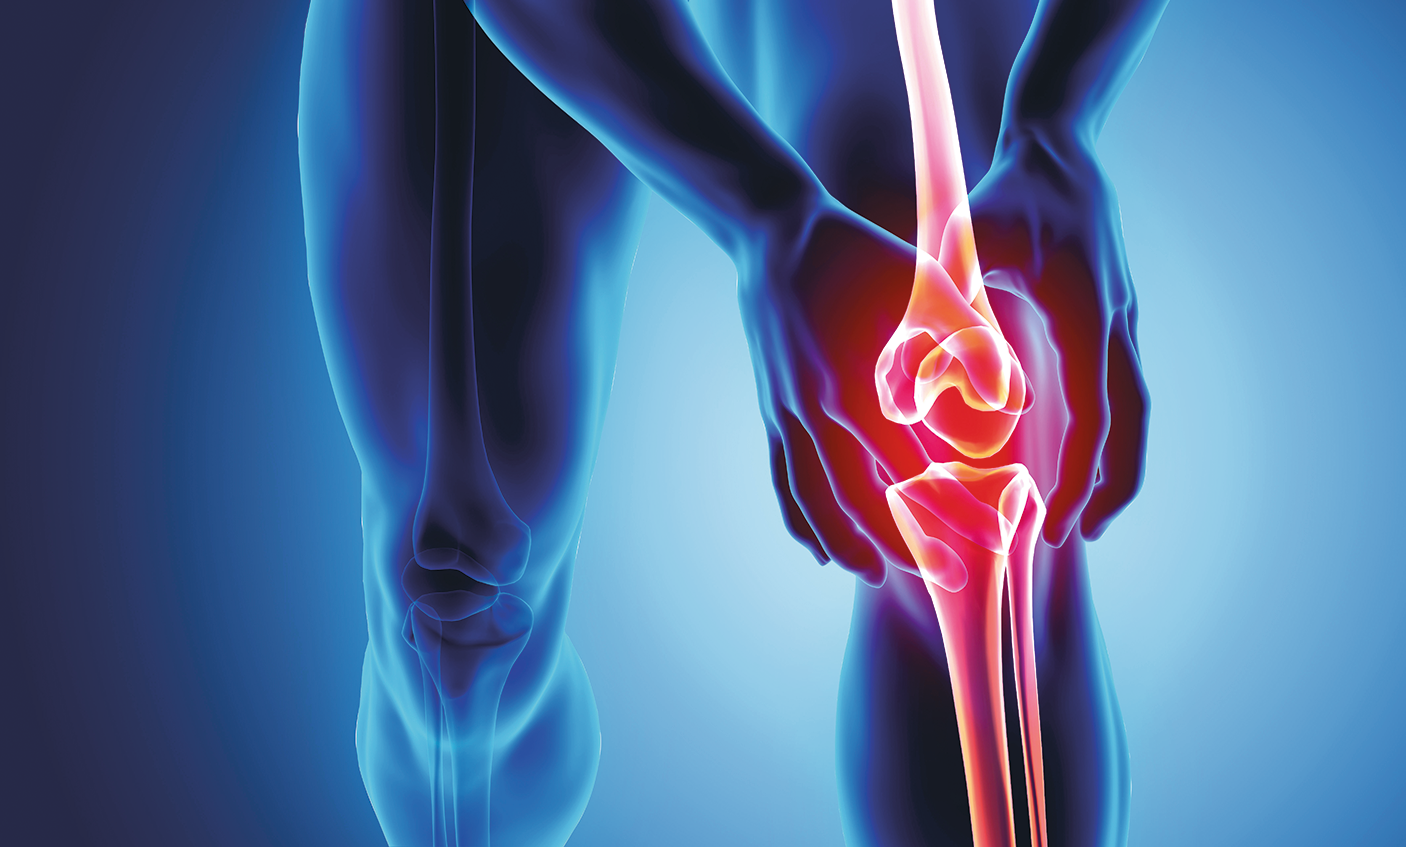

Моменты боли и дискомфорта: визуализация